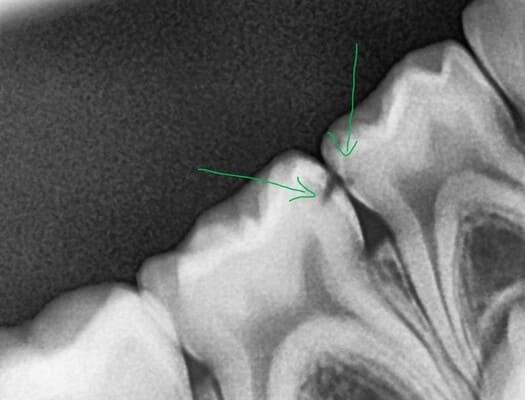

Дівчинка 7 років, перше вересня, гойдалка… Вивих постійного зуба: якщо в такій ситуації зволікати, дитина може втрати постійний зуб назавжди. Батькам порекомендували нас і пацієнти одразу приїхали. Через складність і травматичність процедур вирішено проводити лікування в анестезіологічному супроводі. Зуб поставлений на місце (репонований), проведена хірургічна обробка і ушивання рани губи. Останнє фото через рік після травми: зуб на місці і корінь продовжує розвиватись, губа повністю загоїлась